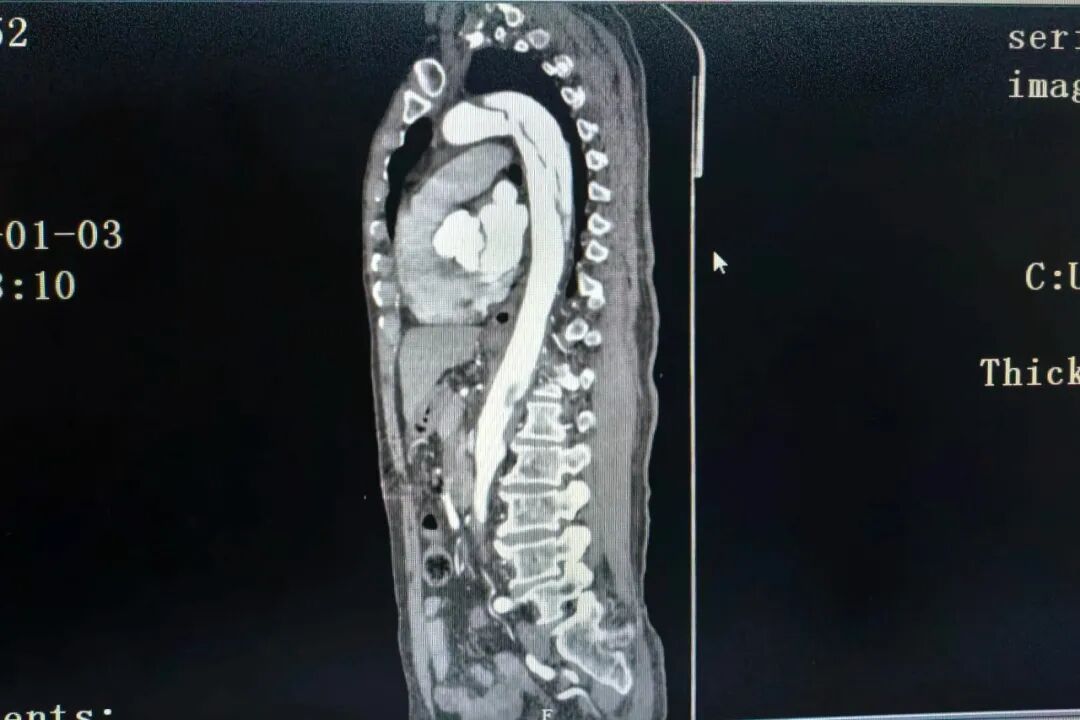

据了解,该名患者为老年男性,既往有慢性胃炎、高血压病史,于2026年1月3日无明显诱因突发胸痛,以胸骨中下段为甚,呈剧烈疼痛,伴大汗淋漓、烦躁不安及恶心症状,持续数分钟无法自行缓解,遂来医院就诊。入院后急诊完成首份心电图检查,提示“窦性心动过缓,ST-T段改变”,考虑到患者症状凶险,为其进行急诊CTA检查,最终确诊为:主动脉夹层(DeBakey Ⅲ型,Stanford B型),高血压危象。给予控制血压、止痛等积极抢救处理后,患者被转入心血管内科进一步治疗。

图片图片

(术前CT造影)

患者病情危急、进展迅猛,心血管内科团队第一时间组织多学科讨论,综合其年龄、基础疾病与病情特点,全面评估手术风险后,最终决定采用胸主动脉覆膜支架腔内隔绝术联合左锁骨下动脉覆膜支架植入术的微创治疗方案。经过周密的术前准备,心血管内科团队为患者施行手术,术中精准释放覆膜支架,成功重建血流通路。术后造影显示,胸主动脉支架与左锁骨下动脉分支支架扩张充分,贴壁良好,未见夹层及内漏,远端血流良好,手术达到预期效果。整台手术历时约两小时,术后患者安全返回病房。